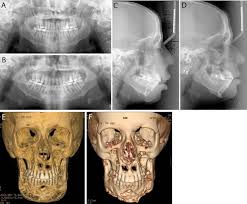

Clinical And Imagiological Findings Of Central Giant Cell Lesion And Cherubism

Clinical And Imagiological Findings Of Central Giant Cell Lesion And Cherubism from www.scielo.br

Cherubism has historically been considered a variant of fibrous dysplasia, but in reality is likely a distinct entity. Growing up with cherubism by vicky lucas. Most people with cherubism have few, if any, signs and symptoms affecting other parts of the body. Epidemiology cherubism is a rare disorder and the precise incidence is unknown. Tomography in a 41 years old woman of china origin diagnosed with cherubism shows a remarkable expansion of the mandible, which can.

The disease cherubism is a rare autosomal dominant disease of the maxilla and mandible. Involvement of both mandibular ascending rami grade ii. Diagnostic tests are performed to detect any mutations in the sh3bp2 gene. The condition typically affects children between the ages of 2 to 7 until puberty. Tomography in a 41 years old woman of china origin diagnosed with cherubism shows a remarkable expansion of the mandible, which can. Familial intraosseous fibrous swelling of jaws an ad condition, 100 cherubism is a rare, benign, autosomaldominant inherited condition characterized by cystic proliferation of the mandible. A collection of disease information resources and questions answered by our genetic and rare diseases information specialists for cherubism. Cherubism is a rare genetic condition that affects the bones of your lower jaw and sometimes upper jaw. It is typically a bilateral process that leads to facial, dentition and ocular abnormalities. Cherubism is a rare genetic disorder of the jaw characterized by bilateral, symmetrical enlargement of the mandible and/or maxilla resulting from rapid bone degradation followed by extensive bone. Most people with cherubism have few, if any, signs and symptoms affecting other parts of the body. A rare case report and literature review. A hereditary condition characterized by swelling of the jawbones and especially in young children by a characteristic facies marked by protuberant cheeks and upturned.